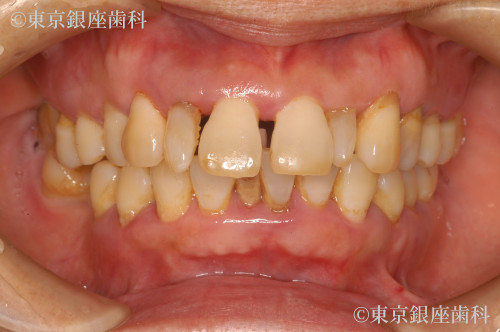

全顎的な重度歯周病による動揺、歯列崩壊をワンデイインプラントで改善した症例

全体的に歯がぐらつき出血し、何本か抜けてしまった。日に日に悪くなっている。他院で総入れ歯しかないと言われた。

全顎的に歯周病が進行し早急に抜歯が必要な歯が何本もあった。咬合改善、審美回復も望まれていたため全ての歯を抜歯し上下ワンデイインプラントを計画した。その際、左上顎洞部分の骨が薄いことから、人工骨を用いて骨量を増やしインプラントの安定を図るサイナスリフトも同時に行うこととした。